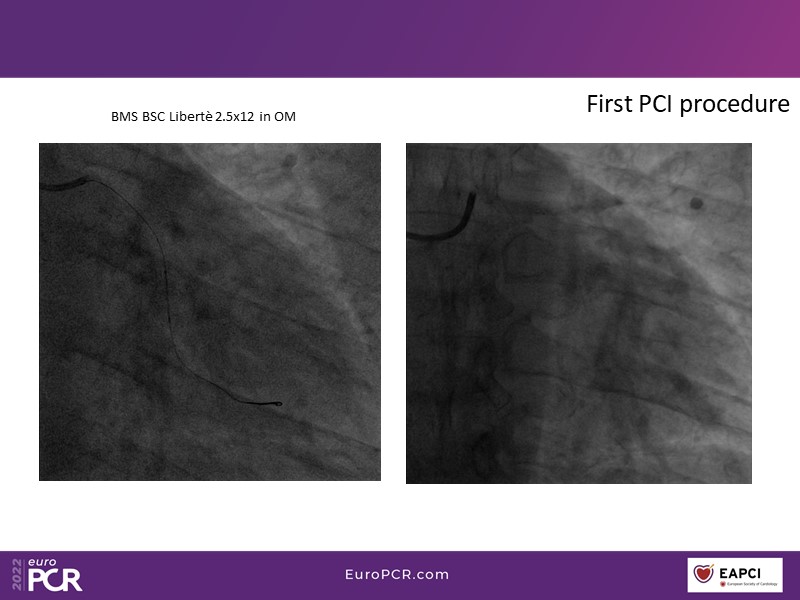

This EuroPCR 2022 session aims to show, based on real-life cases, that even complex coronary disease can be treated without the need for permanent coronary stents. Learn how to prepare the vessel, deliver the therapy, and assess immediate outcomes after "DCB-alone" PCI, discuss de novo, small vessels, and in-stent restenosis cases with follow-up, define what may be an optimal long-term result, refresh the scientific bases, and understand the clinical benefits and safety of paclitaxel DCBs.

- To know how to prepare the vessel, deliver the therapy and evaluate the immediate results after "DCB-alone" PCI

- To discuss de novo, small vessels and in-stent restenosis cases with follow-up and define what may be an optimal long-term result